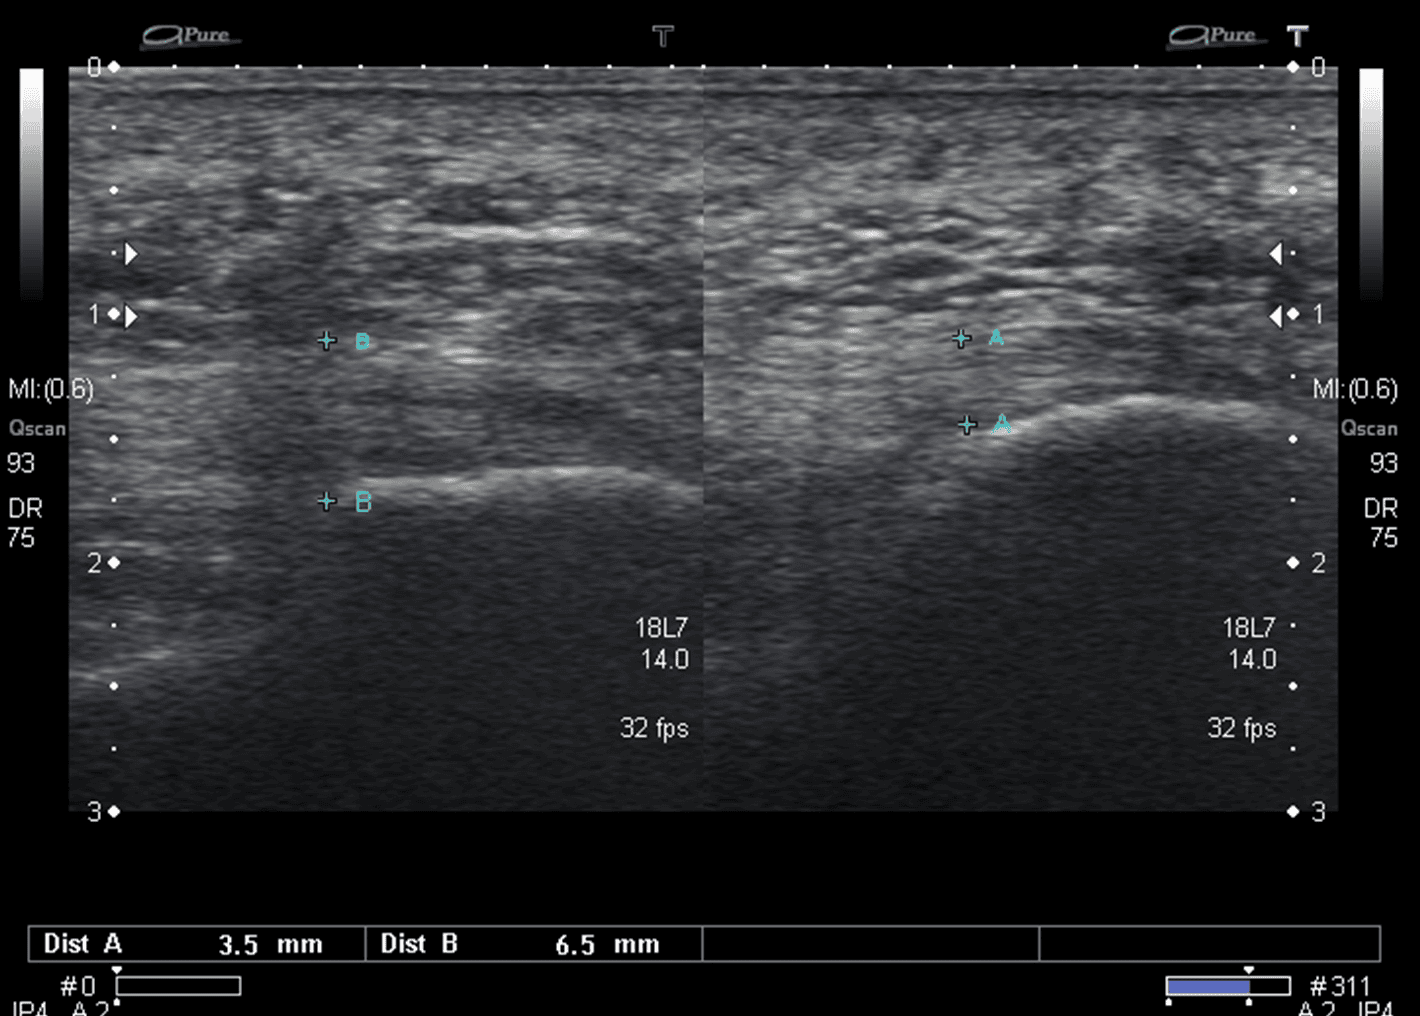

Plantar Fasciitis Ultrasound . Intense therapeutic ultrasound for chronic plantar fasciitis musculoskeletal tissue pain reduction was evaluated in a pivotal clinical trial examining effectiveness, safety, and patient tolerance. Learn how ultrasound technology can treat plantar fasciitis and other soft tissue problems by breaking down the damaged. Diagnosis of plantar fasciitis can be easily verified by ultrasonography with plantar fascia thickness > 4 mm being suggestive of. On ultrasound, plantar fasciitis presents with pf thickening (dashed line, 6.5 mm), a hypoechoic appearance and loss of fibrillar pattern (b).

On ultrasound, plantar fasciitis presents with pf thickening (dashed line, 6.5 mm), a hypoechoic appearance and loss of fibrillar pattern (b). Intense therapeutic ultrasound for chronic plantar fasciitis musculoskeletal tissue pain reduction was evaluated in a pivotal clinical trial examining effectiveness, safety, and patient tolerance. Diagnosis of plantar fasciitis can be easily verified by ultrasonography with plantar fascia thickness > 4 mm being suggestive of. Learn how ultrasound technology can treat plantar fasciitis and other soft tissue problems by breaking down the damaged.